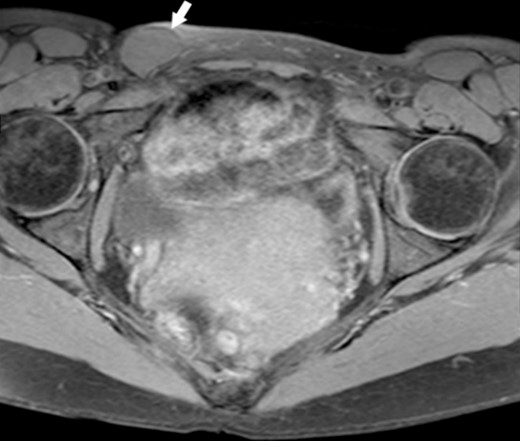

A 44-year-old Caucasian woman presented in our clinic with a painless swelling in the right inguinal region that appeared 10 months before her hospitalisation. A small soft mass measuring 4 × 2 cm2 was found on the physical examination. There were no changes in size or shape in the lesion when performing the Valsalva manoeuvre. Magnetic resonance imaging (MRI) showed an oval cyst measured 3.9/2.6/2.4 cm close to the uterus’s round ligament in the right inguinal channel. The lesion was hypointense in T1- (Fig. 1) and hyperintense in T2-sequence (Fig. 2). An anechoic cyst was observed using ultrasound. The cyst was classified as type I based on Counseller and Black’s classification [2]. Blood analysis showed no pathological changes.

MRI of the Cyst of the Canal of Nuck–T2 sequence. This figure displays the cyst (indicated by the white arrow), showcasing its appearance on a T2-weighted image.